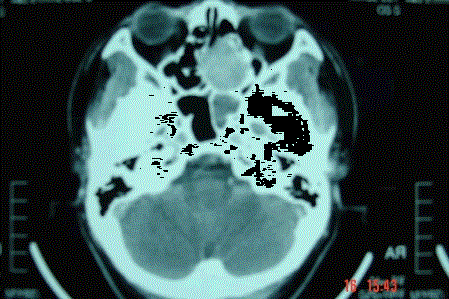

问题 病历摘要: 患者男,37岁,因右鼻塞伴涕中带血4个月入院,患者4个月前始右鼻塞,为间断性,偶有涕中带血,时有流脓性分泌物,并症状渐渐加重。但发病以来患者无头痛、面部麻木和疼痛,无复视及流泪,张口正常。检查:右侧鼻腔总鼻道可见表面光滑、质中、粉红色肿物,触之不易出血。鼻咽黏膜光滑,未见新生物和黏膜糜烂。颈部未及淋巴结肿大。 在活检结果未出来前,你考虑哪些疾病? 提示:鼻窦CT显示:右侧中鼻道-上颌窦窦口区见一软组织密度肿块影,大小约35×5mm,增强扫描中等强化。肿块向外侧破坏上颌窦内侧壁突入上颌窦,向内侧破坏鼻中隔累及左侧鼻腔,向上破坏右侧筛窦下壁。右侧中鼻甲骨质破坏。

选项 A、软骨瘤 B、鼻窦恶性肿瘤 C、血管瘤 D、筛窦黏液性囊肿 E、筛窦浆液性囊肿 F、骨瘤 G、出血性坏死息肉 H、鼻窦真菌病

答案 BDH